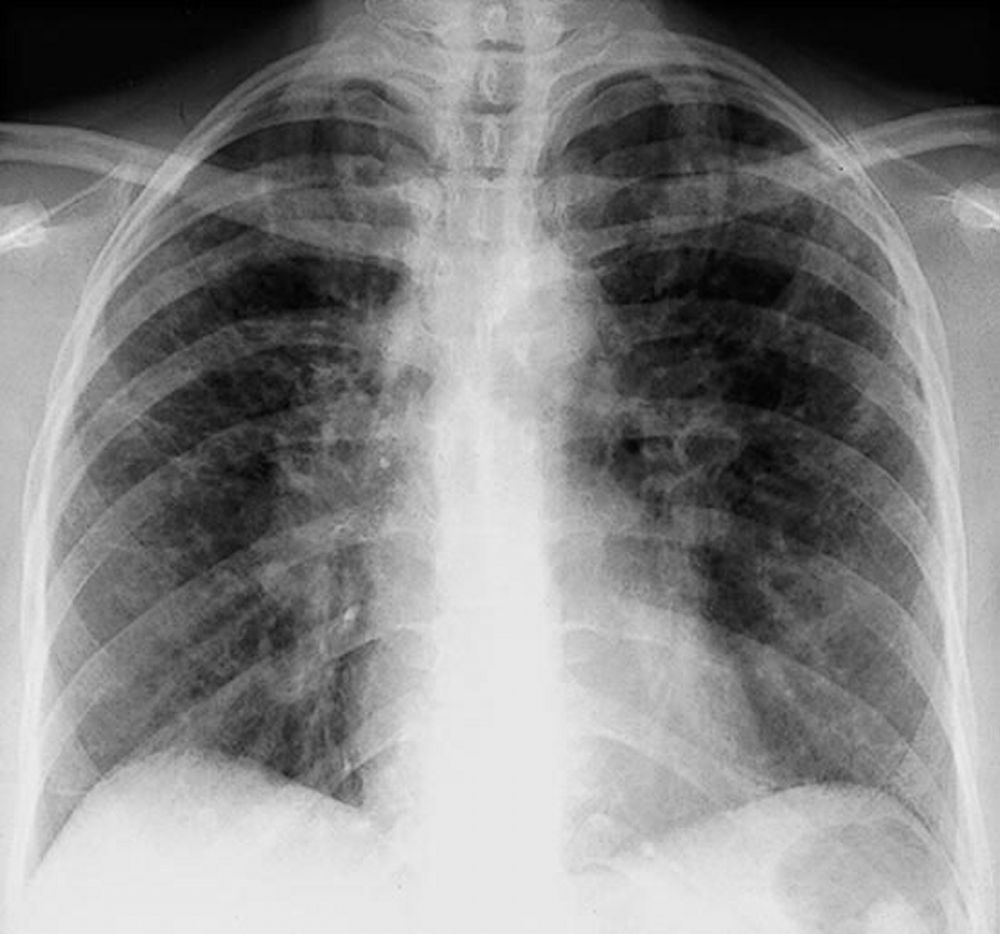

Stadiazione radiografica di Scadding

La radiografia del torace (RX) rimane il punto di partenza per la classificazione della sarcoidosi polmonare, utilizzando il sistema di Scadding che divide la malattia in quattro stadi principali sulla base dei reperti linfo-parenchimali.[1, 12, 13]

| Stadio | Definizione radiografica | Significato clinico e prognostico |

|---|---|---|

| 0 | RX torace normale | Malattia puramente extratoracica o pre-radiologica |

| I | Linfoadenopatia ilare bilaterale (BHL) | Stadio più comune; spesso asintomatico; alta remissione spontanea |

| II | BHL associata a infiltrati parenchimali | Presenza di granulomi sia nei linfonodi che nel tessuto polmonare |

| III | Infiltrati parenchimali senza BHL | Granulomi confinati al polmone; minore probabilità di remissione |

| IV | Fibrosi polmonare diffusa | Presenza di cicatrici permanenti, perdita di volume e cisti |

Tuttavia, la TC ad alta risoluzione (HRCT) è oggi considerata indispensabile per una migliore caratterizzazione. I segni tipici alla HRCT includono noduli a distribuzione perilinfatica (lungo i setti interlobulari e le scissure), ispessimento dei fasci broncovascolari e opacità a “vetro smerigliato” che riflettono un’alveolite granulomatosa attiva.